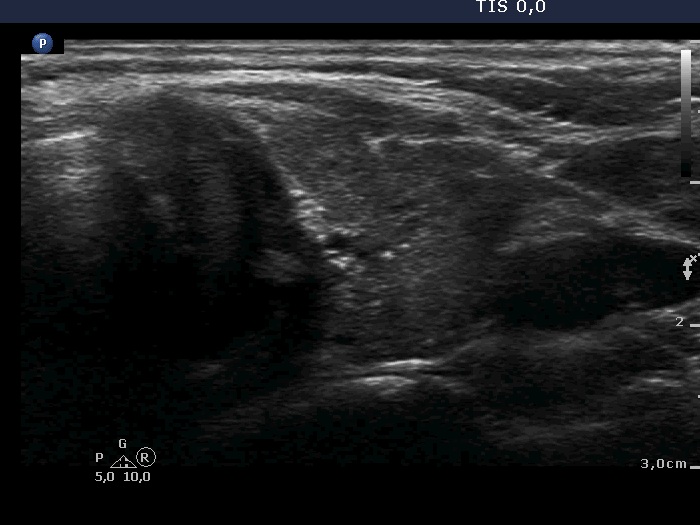

Ultrasonography. The thyroid was minimally hypoechoic and had more hypoechoic areas corresponding to the underlying thyroiditis. There was a nodule in the dorsal part of the left lobe. The nodule was a bit brighter compared to the extranodular tissue but darker compared to a healthy thyroid. Beside macrocalcification, the nodule contained numerous microcalcifications. The latter occurred even outside the tumor. The borders of the nodule were difficult to judge. The lesion presented a combined perinodular and intranodular vascularity.

Depending on the 'normal' reference tissue, the lesion can be regarded as iso/hyperechoic or minimally/moderately hypoechoic, the reference tissue is the non-nodular part of the actual patient or a healthy thyroid, respectively.

This is an example of invasive spread which is characterized by isolated microcalcifications relatively far from the primary tumor focus.